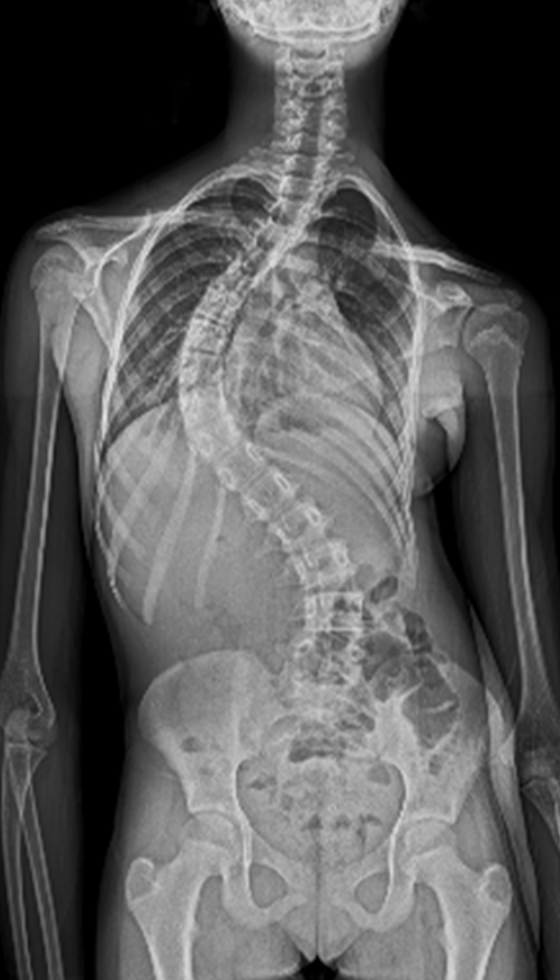

Scoliosis is a common condition characterized by a sideways curvature of the spine, often emerging during puberty. While its origins can vary, most cases are mild. However, without proper attention, severe deformities may lead to significant functional disabilities, impacting lung function and overall well-being.

Gallery : Before - After

After

Before